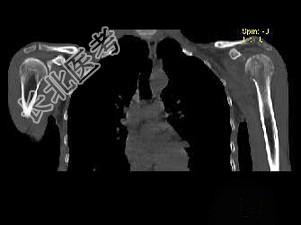

- 单项选择题男,29岁, 行走时不慎跌倒,曾拟为左肱骨头骨折并行固定, 但半年后疼痛未减轻,触压局部骨质松软, 如触及乒乓球感,明显叩击痛, 结合图像,最可能的诊断是 ( )